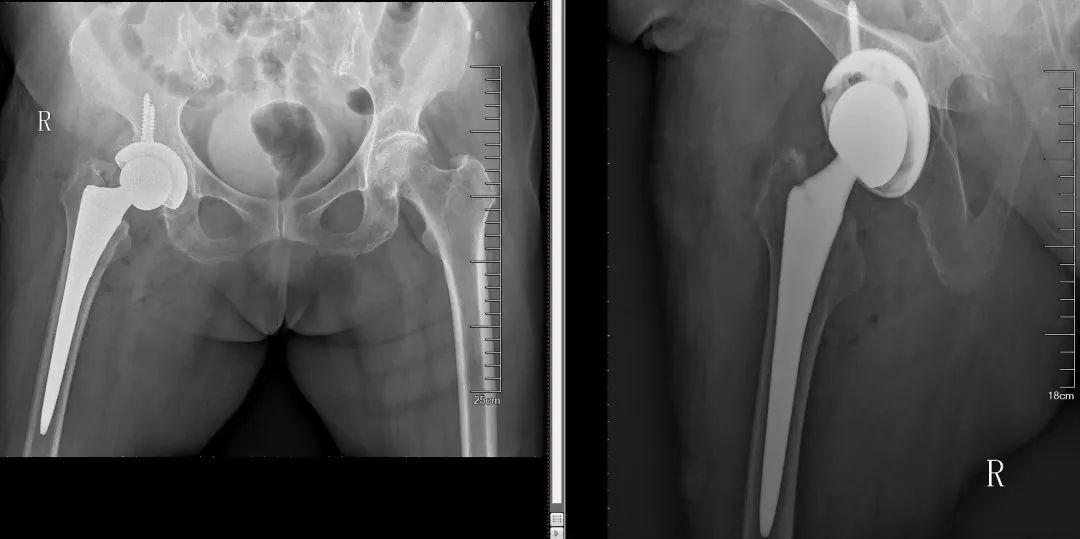

朱奶奶成功接受了人工髋关节置换手术,现在是术后的6个月,朱奶奶已经丢掉轮椅,基本恢复正常行走。

第二,现在人工髋关节置换手术技术越来越成熟,手术时间短、出血少、恢复快,一般无特殊情况,能做到术后当天或第二天下地站立并练习行走,是目前最好的治疗手段。